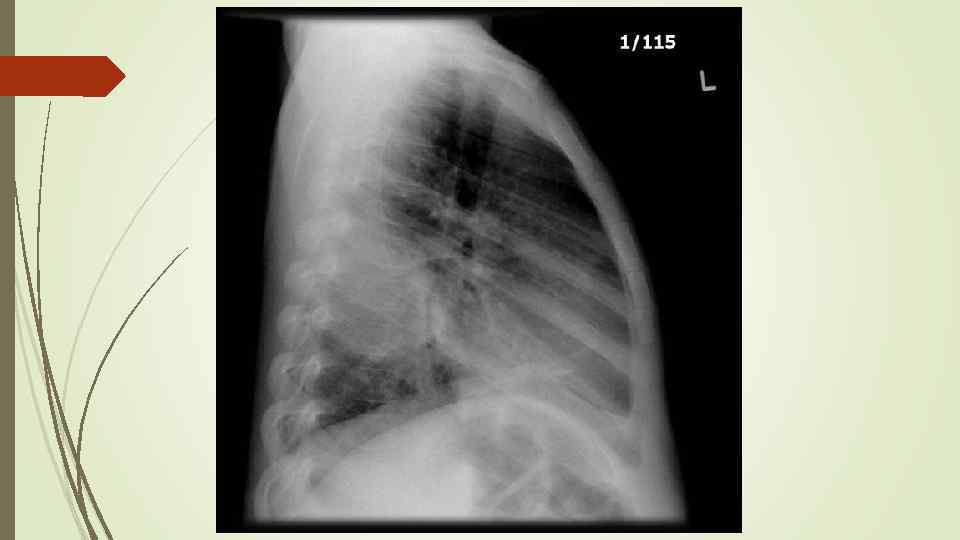

Бронхопневмония Характерно наличие двухсторонних множественных очаговых теней. Контуры очагов нечеткие, интенсивность тени небольшая. Инфильтрация неоднородна. Мелкие, малоинтенсивные очаги не всегда выявляются на снимках. Легочный рисунок усилен на всем протяжении легких. Корни расширены, не структурны. Как правило, отмечается реакция плевры, могут быть и экссудативные плевриты.

Бронхопневмония Характерно наличие двухсторонних множественных очаговых теней. Контуры очагов нечеткие, интенсивность тени небольшая. Инфильтрация неоднородна. Мелкие, малоинтенсивные очаги не всегда выявляются на снимках. Легочный рисунок усилен на всем протяжении легких. Корни расширены, не структурны. Как правило, отмечается реакция плевры, могут быть и экссудативные плевриты.

bronhopneumoni

bronhopneumoni